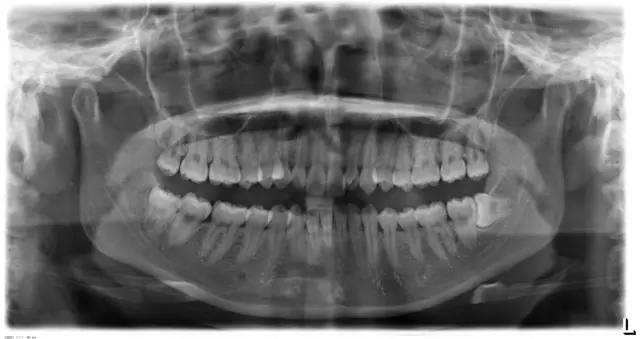

Damon 病例分享:安氏 II 類(lèi)二分類(lèi)露齦笑的矯治(董一磊)

患者信息